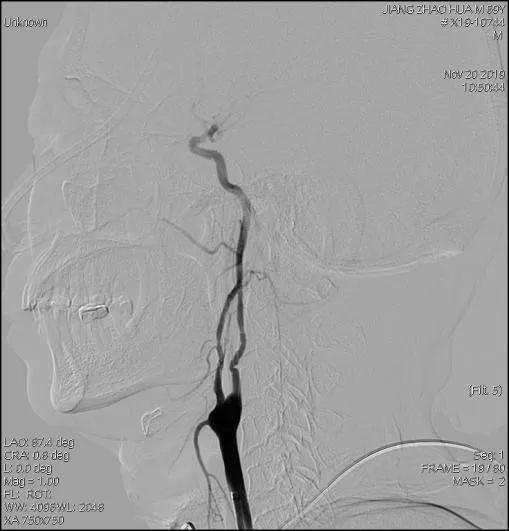

术前影像

患者取仰卧位,常规消毒铺巾,Seldinger技术穿刺右股动脉,置入股鞘,引入8F导引导管至左侧颈总动脉分叉近端,造影提示:左侧颈内动脉近段肿瘤侵犯至狭窄,长约15mm,远端走形正常;后引入FilterWire EZ保护伞顺利通过狭窄段至C1远端,释放保护伞;引入4.5mm*16mm WILLIS®覆膜支架,精准定位后,缓慢球囊扩张释放支架。